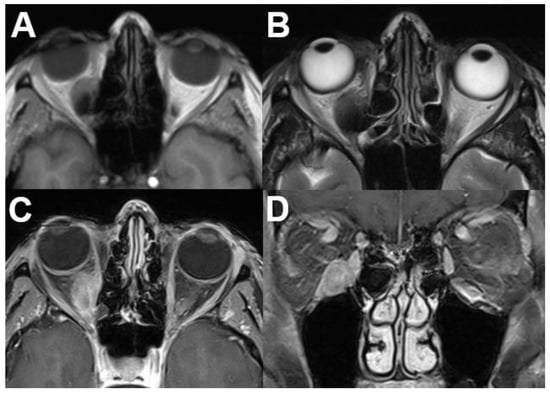

3.3. Extraconal Tumors

3.3.1. Capillary Hemangioma

3.3.2. Lymphoma

3.3.3. Tumors of the Lacrimal Gland